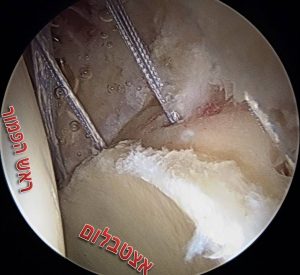

את הלברום משחזרים בעזרת שתל גיד שמוכנס למפרק דרך הפורטלים של הניתוח ומקובע למקומו בעזרת עוגנים באותו האופן שבו מתקנים לברום מקורי. שתל הגיד יכול להיות מתורם או שתל גיד עצמי (אלוגרפט או אוטוגרפט בהתאמה), באופן כללי עדיף להשתמש בשתל גיד מתורם על מנת להמנע מסיבוכים עקב הפרוצדורה לקצירת הגיד. עד לא מזמן, החלק המסובך ביותר בניתוח היה מדידת האורך של האזור שחסר בו לברום וזאת לצורך הכנת שתל בגודל מתאים, בשיטות העדכניות משתמשים בשתל גיד ארוך מראש ובסיום הפרוצדורה חותכים את השארית כך שנעשה שימוש באורך מדוייק של גיד. בעיה נוספת שהיה צורך לפתור היא נקודת החיבור בין הלברום המשוחזר לזה הקיים, לבעיה הזו פותחו שני פתרונות – האחד להחליף את הלברום כולו והשני לשמור רקמה ככל שניתן בלברום הקיים ולאחר ההשתלה לבצע חפיפה בין הלברום החדש לישן.